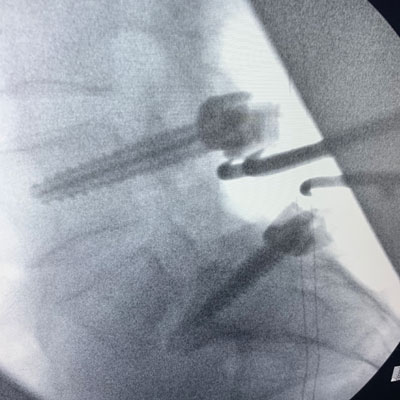

The patient underwent a decompressive laminectomy from L4-S1 with decompression of the L5 nerve roots and instrumented L4-S1 fusion (Figs. 2 and 3). Intraoperatively she had a very loose L5 lamina and had thickened degenerative ligamentous material severely flattening the L5 nerve roots at the level of the lysis defect. The patient tolerated surgery well with significant relief of back and leg pain.

Figure 2 – Fluoroscopic sagittal and AP images demonstrating post-pedicle screw placement at L4 and S1.